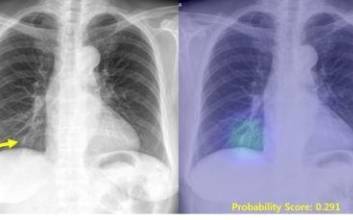

국내 AI, 폐암·폐결핵·폐렴·기흉 판독 '의사보다 정확'

국내 대학병원과 IT 기업이 개발한 인공지능(AI)이 폐암·폐결핵·폐렴·기흉 등 4대 흉부 질환을 98% 이상 정확하게 판독해 냈다.서울대병원 영상의학과 박창민 교수와 소프트웨어 개발 기업 루닛 공동 연구팀은 자체 개발한 AI 보조 진단 시스템을 폐 결절을 포함한 4대 흉부 질환 진단에 적용한 결과, 질환을 선별하고 위치까지 찾아내는 정확도가 98% 이상에 달했다고 1일 밝혔다.흉부 4대 질환은 전 세계적으로 발병 빈도와 사망률이 높아 정확한 진단으로 조기에 치료하는 것이 중요하다.연구팀은 이번 AI 시스템 개발을 위해 4대 흉부 질환과 관련된 총 9만8621건의 흉부 X-선 영상 자료 결과를 AI 진단 학습에 활용했다.이 AI는 서울대병원·보라매병원·강동경희대병원·을지대병원·프랑스 그르노블 대학병원 등 국내외 5개 병원에서 이뤄진 진단 정확도 평가에서 평균 97% 이상의 높은 점수를 받았다.또 영상의학과 전문의를 포함한 의사 15명과 비교 평가에서도 AI의 정확도는 98.3%로 흉부영상의학 전문의의 93.2%보다 높았다. 의료진 측면에서는 AI의 보조를 받을 경우 판독 능력이 최대 9%p까지 높아지는 효과도 관찰했다.연구팀은 "AI 시스템은 환자의 흉부 X-선 영상을 분석해 이상 소견이 있는 부위를 표시하고, 그 가능성을 확률값으로 제시해 준다. 이를 활용하면 보다 손쉽게 영상 진단을 내릴 수 있을 것으로 보인다"고 말했다.이 AI 시스템은 향후 식품의약품안전처 의료 기기 승인을 거쳐 실제 환자 진단에 사용될 전망이다.이번 연구 결과는 미국의사협회(JAMA)가 발행하는 권위지인 '자마 네트워크 오픈' 최근호에 게재됐다. 권오용 기자 kwon.ohyong@jtbc.co.kr 2019.04.02 07:00